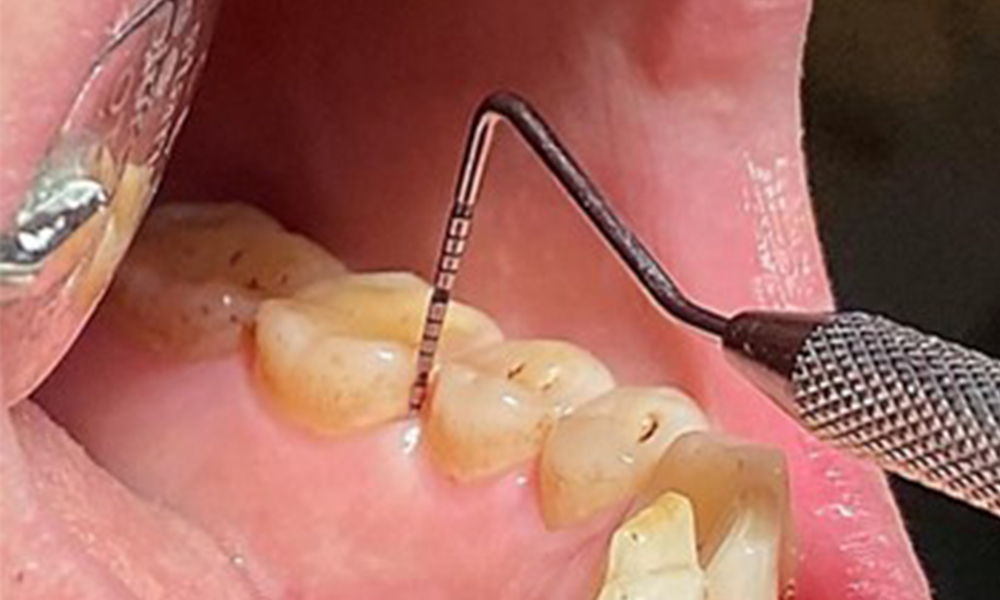

En raison d'un état de santé général par ailleurs favorable, les besoins déterminés lors de l'examen intra-oral seront déterminants pour le traitement. Il sera essentiel de déterminer périodiquement les profondeurs de sondage. Le saignement gingival diminue chez les fumeurs, c'est pourquoi le diagnostic clinique de la parodontite ne peut se faire que par sondage (Fig. 7). En se concentrant exclusivement sur la détermination des indices de saignement, on risque d'occulter une parodontite ou une gingivite existante. (5)

- Il est important de documenter les résultats obtenus lors du rendez-vous thérapeutique. L'état du saignement au sondage (BOP), qui permet de mesurer la profondeur des poches parodontales aux premiers stades de la maladie, doit être déterminé lors de chaque rendez-vous. Cette mesure est particulièrement importante chez les fumeurs en raison de la diminution de la perfusion des tissus.